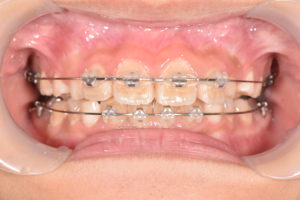

Ⅰ期治療として上顎には急速拡大装置、下顎にはバイヘリックスを用いることで狭窄歯列の拡大を行い、前歯部のスペース不足の改善を行った後に、マルチブラケットを併用することで歯列の配列を行った。前歯部の配列終了後舌側に保定ワイヤーで歯牙の固定を図り治療終了となった。